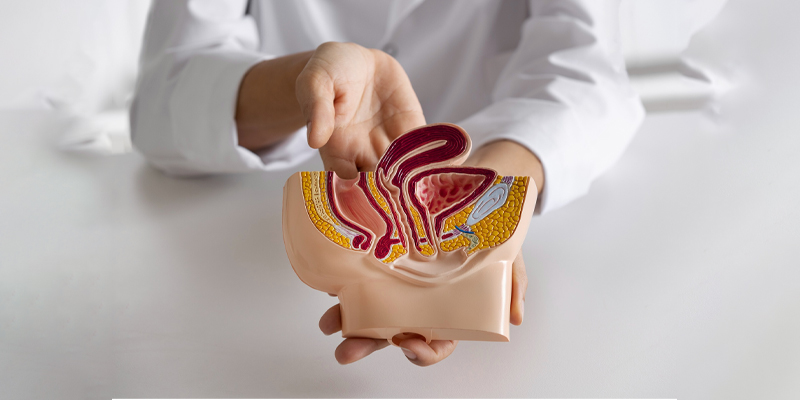

Benign Prostate Enlargement (BPH)

Minimally Invasive Prostate Procedures

Urological Cancers